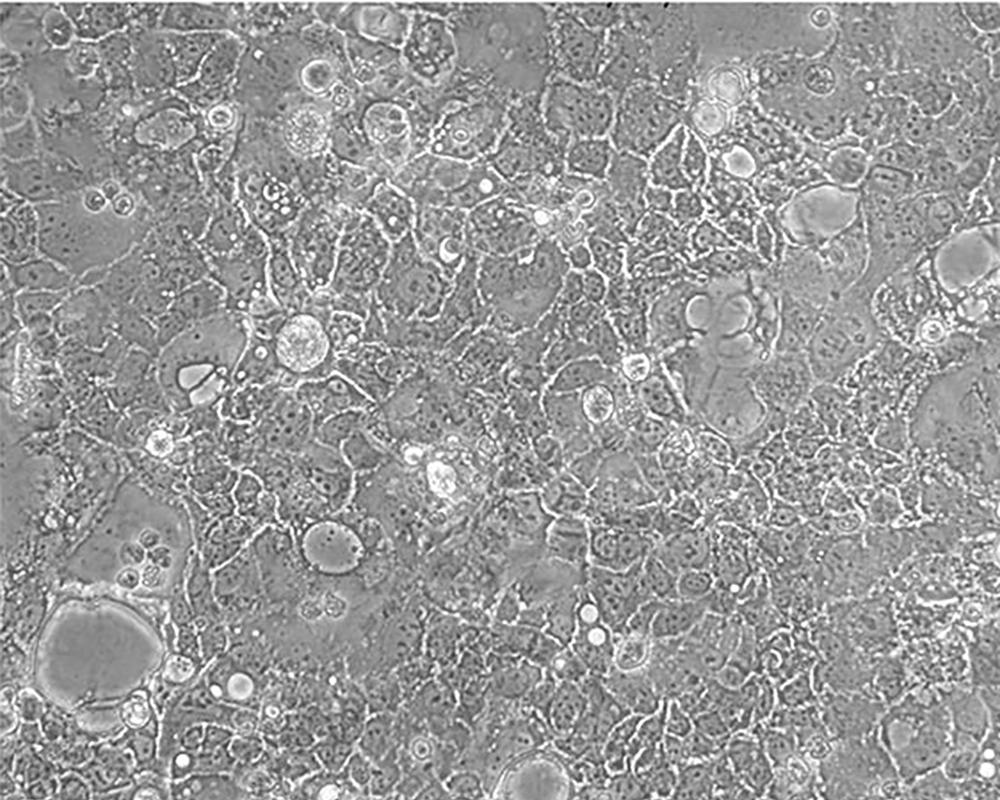

Caco-2

產(chǎn)品名稱 Caco-2

中文名稱 人結(jié)直腸腺癌細胞

組織來源 結(jié)腸腺癌;男性

生長特性 adherent

形態(tài)特征 epithelial

細胞描述 Upon reaching confluence, the cells express characteristics of enterocytic differentiation. Ref Caco-2 cells express retinoic acid binding protein I and retinol binding protein Ⅱ.